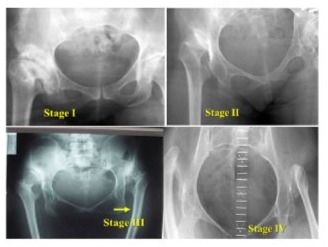

We present our classification for the femoral dysplasia Figure 1.

Stage I - Mild torsion. The femoral canal is almost normal, and it could be associated with any type of Crowe, Kerboul, or Eftekhar stage A, B or C.

Stage II - Important torsion of the diaphysis and metaphysis. It could be associated with any type of Crowe, Kerboul, or Eftekhar C or D. It is a major indication for diaphyseal osteotomy or trochanterotomy during a THA.

Stage III - Severe torsion of the shaft, almost 900 to the condylar axis - a large medullary diameter of the metaphysis is perpendicular to the large diameter of the diaphysis canal. Excellent indication for triple femoral osteotomy.

Stage IV - Caricatural, a caricature of the proximal femur.

Figure 1: Femoral classification of DDH in adults.